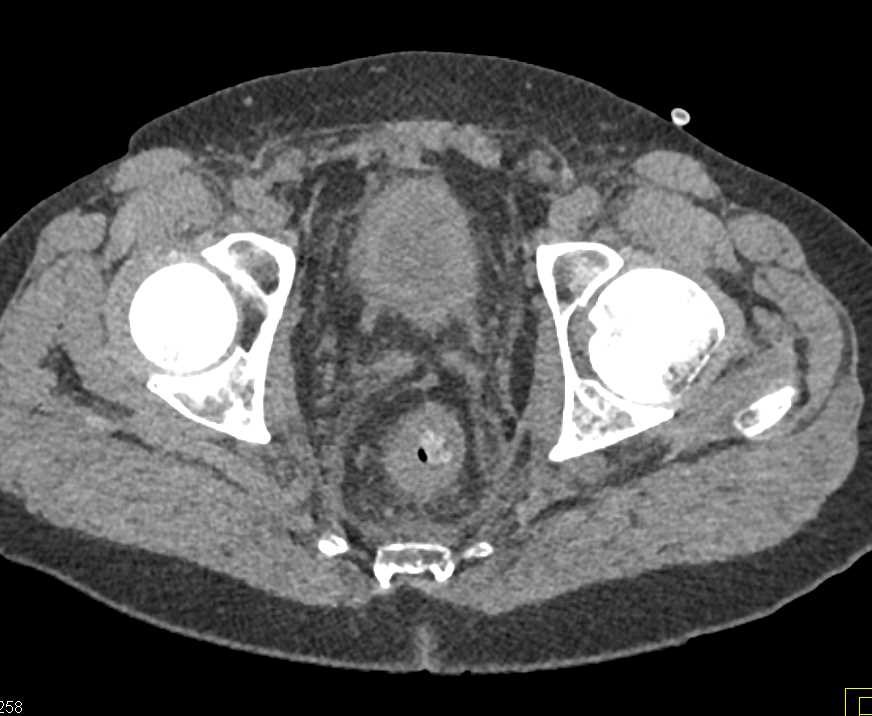

Pseudomembranous Colitis Right Colon